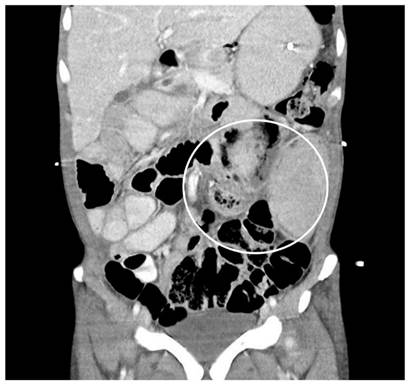

Surgical time was scheduled for a gastric bypass surgery where gastrojejunostomy was performed using conventional technique. On the fifth postoperative day, he presented clinical deterioration due to febrile episodes, abdominal pain, and tachycardia. A new abdominal tomography was performed, reporting an intra-abdominal collection of pus on the left flank of 12 x 12 x 5 cm secondary to the jejunal fistula process. Hence, percutaneous drainage management of the collection was performed by interventional radiology and drainage catheter placement. In addition, an EGD was performed to conduct a pyloric exclusion technique with an Ovesco (over-the-scope-clip) device for managing the jejunal fistula, which was technically successful.

Hacia el quinto día posoperatorio presentó deterioro clínico dado por episodios febriles, dolor abdominal y taquicardia, por lo que se realizó una nueva tomografía abdominal que reportó una colección intraabdominal en el flanco izquierdo de 12 x 12 x 5 cm secundaria al proceso fistuloso yeyunal (Figura 2).

Se realizó el manejo de la colección con drenaje percutáneo por radiología intervencionista y alojamiento de catéteres de drenaje en el que se obtuvo 150 mL de contenido purulento e intestinal, con lo que se logró controlar el proceso infeccioso y optimizar la condición clínica del paciente. 3 días después del drenaje percutáneo, teniendo en cuenta los hallazgos intraoperatorios y la gastroyeyunoanastomisis laterolateral, se decidió realizar manejo endoscópico de la fístula yeyunal proximal por medio de exclusión pilórica, para disminuir el flujo del contenido intraluminal por el asa comprometida, concomitantemente con manejo farmacológico multimodal con inhibidor de bomba de protones (IBP), opioide, antidiarreico y nutrición parenteral. Dadas las comorbilidades del paciente y en busca del procedimiento menos invasivo, se decidió realizar dicha exclusión pilórica con el dispositivo Ovesco, teniendo en cuenta la adecuada funcionalidad de la gastroyeyunoanastomosis, con la que se obtuvo éxito técnico (Figura 3).